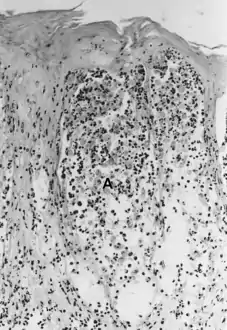

انحلال الأشواك (بالإنجليزية: Acantholysis) هو فقدان الارتباط بين الخلايا مثل الجسيمات الرابطة مما يتسبب بفقدان الالتصاق بين الخلايا الكيراتينية[1] كما يظهر في مرض الفقاع الشائع.[2] هذه الحالة غير موجودة في الفقعان الفقاعي مما يجعله مفيدا في التشخيص التفريقي.

![]() الحمى القلاعية - انحلال الأشواك في عينة جلدية. يمكن ملاحظة نخر الطبقة الشائكة، وملاحظة الخلايا الكيراتينية طائفة من السائل الحويصلي. الحمى القلاعية - انحلال الأشواك في عينة جلدية. يمكن ملاحظة نخر الطبقة الشائكة، وملاحظة الخلايا الكيراتينية طائفة من السائل الحويصلي. | |

يمكن ملاحظة هذه الحالة النسيجية في عدوى الهربس وعدوى فيروس جدري الماء النطاقي (الهربس النطاقي وجدري الماء).